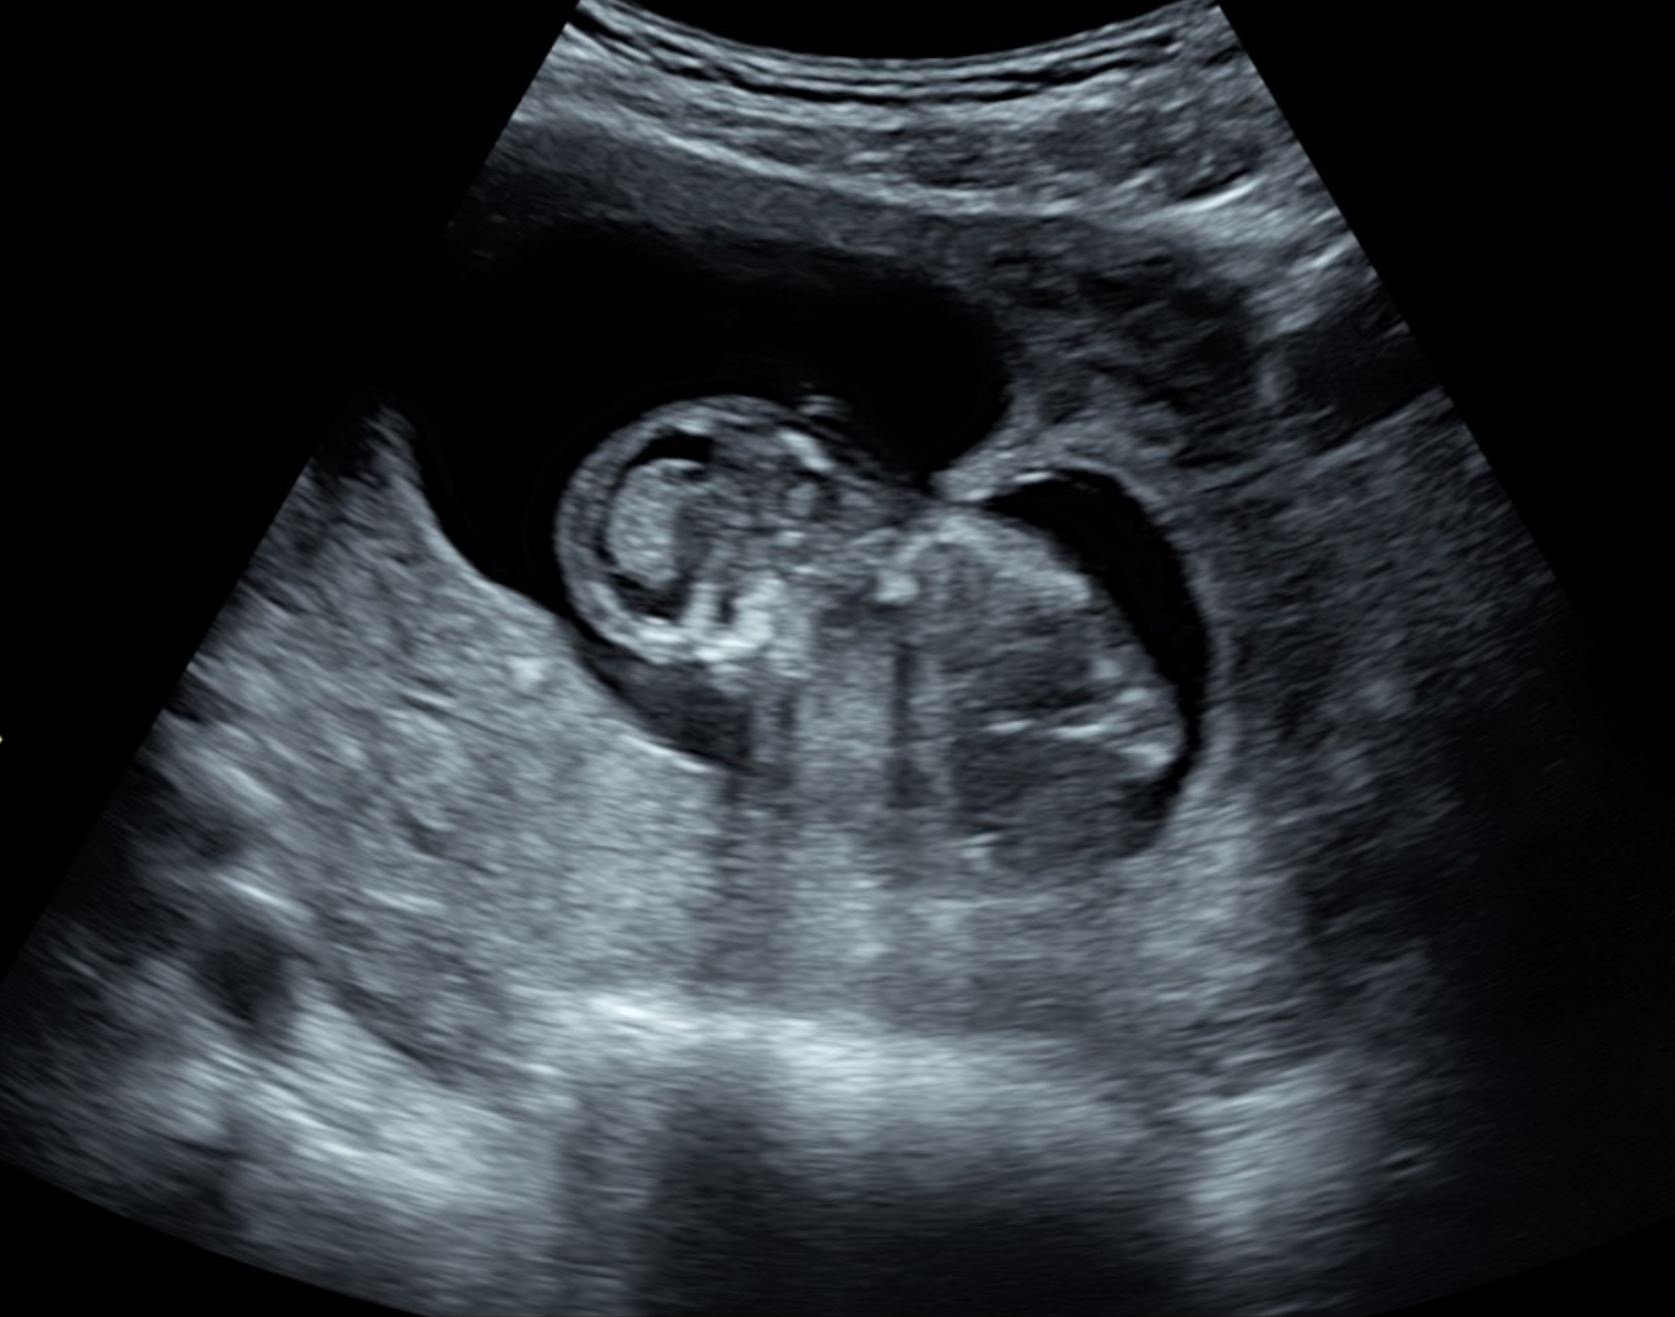

This option allows visualization of the image with a 3D effect. This shows increased visual impressions of the pelvic structures. Additionally, this option is often used to demonstrate the external features of specifically separated pelvic structures and adds some depth to the displayed image. However, this technique is employed more in obstetrics than gynecology. Figure 3 displays an image in the SRI option.

Figure 3. Surface rendering images used to visualize a 19 weeks and 6 days fetal profile.